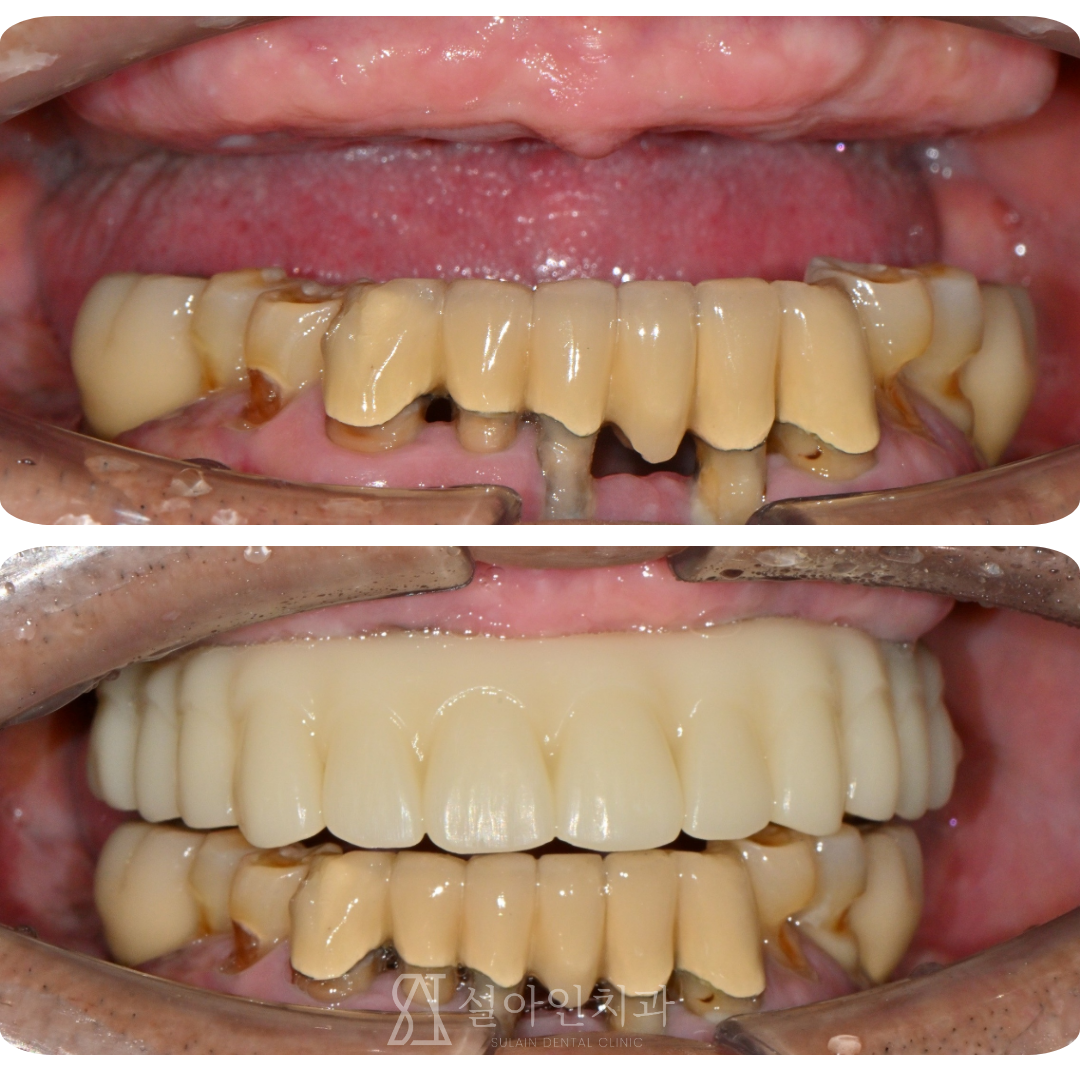

임플란트 수술 다음날, 바로 고정 치아로 식사했습니다. 상악 완전 무치악 환자의 올온엑스(All-on-X) 임플란트 치료 사례